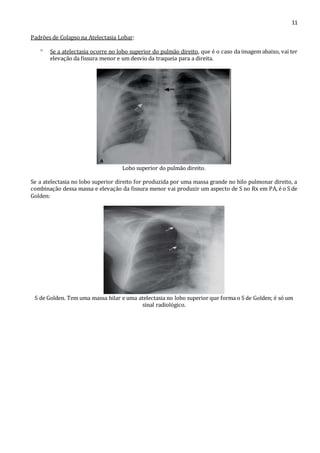

II. Sexo feminino, 97 anos:

Opacificação de todo o hemitórax esquerdo. Em PA e em P, mostrando marca-passo e eletrodos no

coração. Mostra uma densidade na região do hilo. É um carcinoma broncogênico levando a atelectasia de

todo o pulmão.